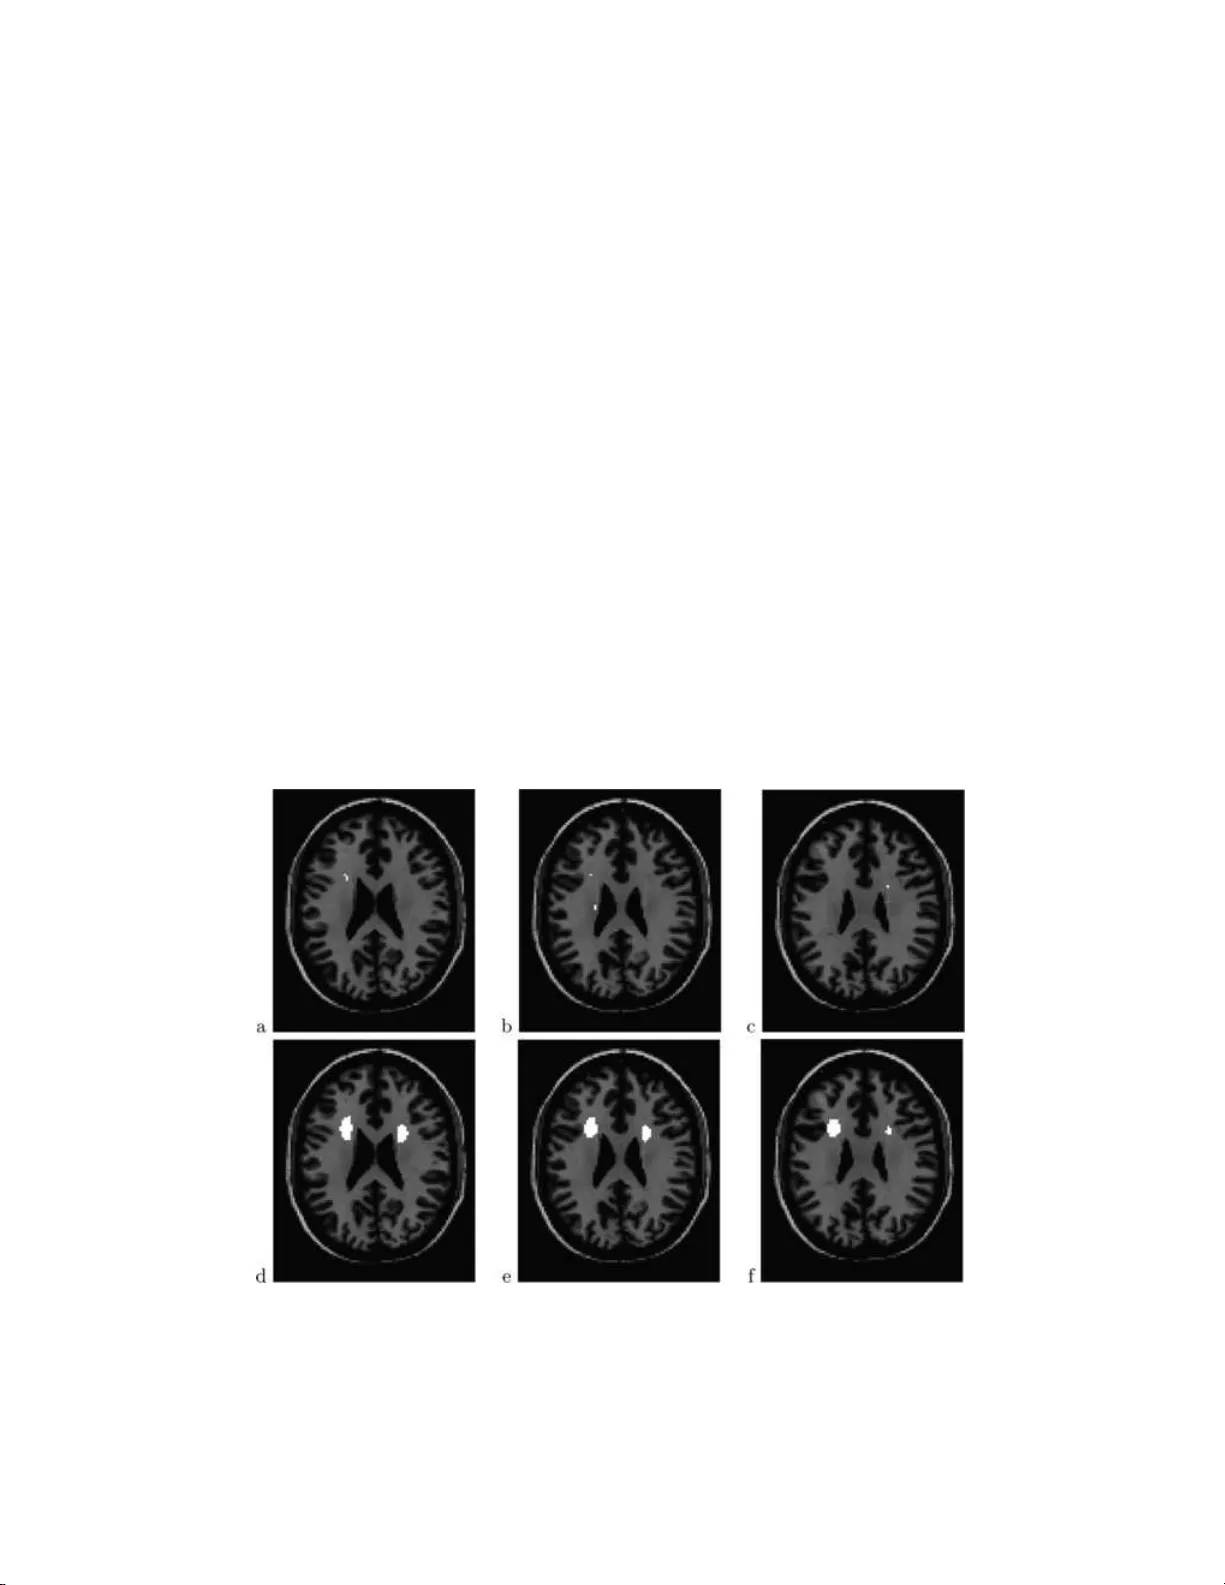

다음 단계는 다중 비교 문제에 대한 거짓 발견율(FDR) 제어이다. 저자는 Storey·Taylor·Siegmund(2004) 방법을 적용해 q값을 추정하고, 목표 FDR 수준(예: 0.05) 이하인 voxel을 ‘흥미로운’ 영역으로 선정한다. 기존 뇌 영상 연구에서 흔히 쓰이는 전체 뇌 영역에 대한 가족 오류율(FWER) 제어와 달리, FDR는 선택적 검출에 초점을 맞추어 보다 높은 검출력을 제공한다.

또한, 뇌 영상 데이터는 공간적 연속성을 갖기 때문에, 저자는 검정통계량 지도에 로컬 평균(smoothing) 필터를 적용해 잡음 분산을 감소시켰다. 공간 평균은 인접 voxel들의 통계량을 평균함으로써 신호 대 잡음비를 향상시키며, 경험적 영가설을 재추정해 스무딩 후에도 올바른 영가설 밀도를 유지한다. 이 과정은 FDR 기반 검정의 검출력을 크게 높이며, 실제 데이터에서 의미 있는 영역을 더 넓게 포착한다.

실험에서는 6명의 정상군과 6명의 난독증군, 총 12개의 확산 방향 지도(95×79×68 voxel)를 사용하였다. 모든 이미지가 MNI 템플릿에 정합(registration)된 후, 백색질 마스크(20,931 voxel) 내에서 분석을 수행했다. 경험적 영가설과 공간 스무딩을 적용한 결과, 기존 FA 기반 분석이 탐지한 120 voxel에 비해 수백 개에 달하는 voxel에서 유의한 방향 차이가 발견되었으며, 특히 상부 좌측 백색질 영역에서 정상군과 난독증군 사이에 뚜렷한 방향 전이 차이가 관찰되었다.